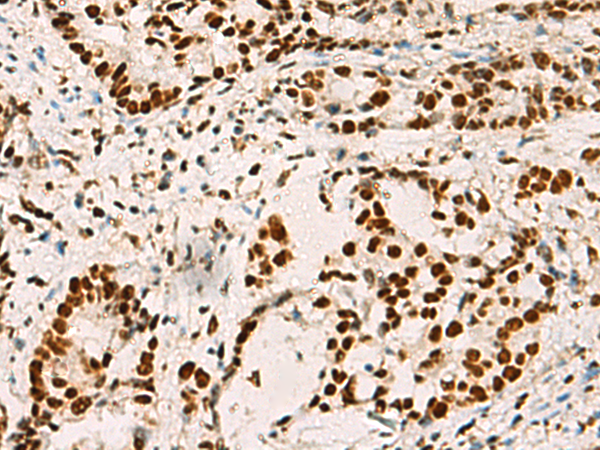

ELISA, IHC |

IHC positive control: |

Human colorectal cancer and Human cervical cancer |

IHC Recommend dilution: |

50-200 |